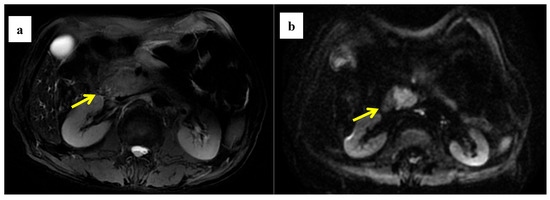

Figure 5.

A 61-year-old man was found to have a tumor with a head size of about 2.1 cm in the pancreas, which was pathologically confirmed to be pancreatic ductal adenocarcinoma after surgery; we found that the tumor was characterized by a low ADC value, low D value, and high f value after quantitative MRI measurement. He was found to have a local recurrence at follow up 9 months after surgery and died 15 months later. MRI T2 (a), DWI (b), and ADC map (c) showed solid mass in the head of pancreas measured ADC measurements of 1.07 × 10−3 mm2/s, D value of 0.91 × 10−3 mm2/s, and f value of 0.47. Immunohistochemical staining showed an abundance of CAFs in the stroma ((d) α-SMA, ×10), carcinoma cells with higher expression of VEGF in the cytoplasm ((e) VEGF, ×10), and HIF-1a in the nuclear ((f) HIF-1α, ×20). These findings suggested that the tumor microenvironment was active with a higher hypoxia level.